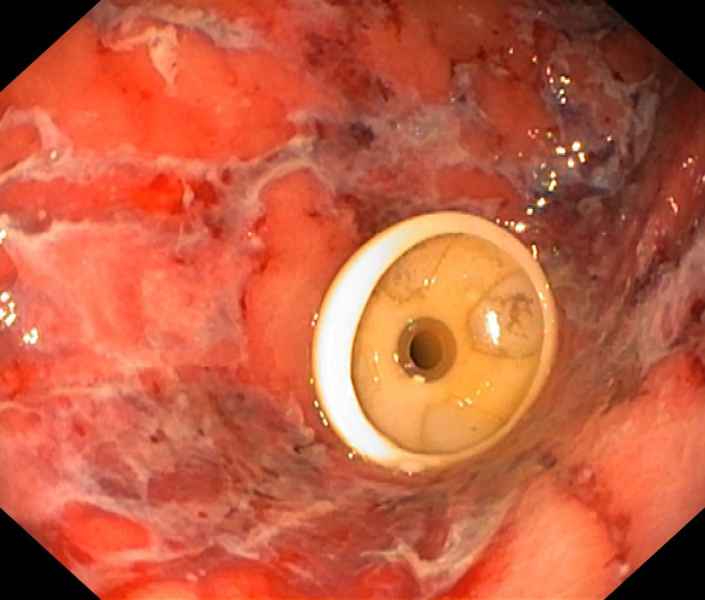

An uninvited guest

Fotografia